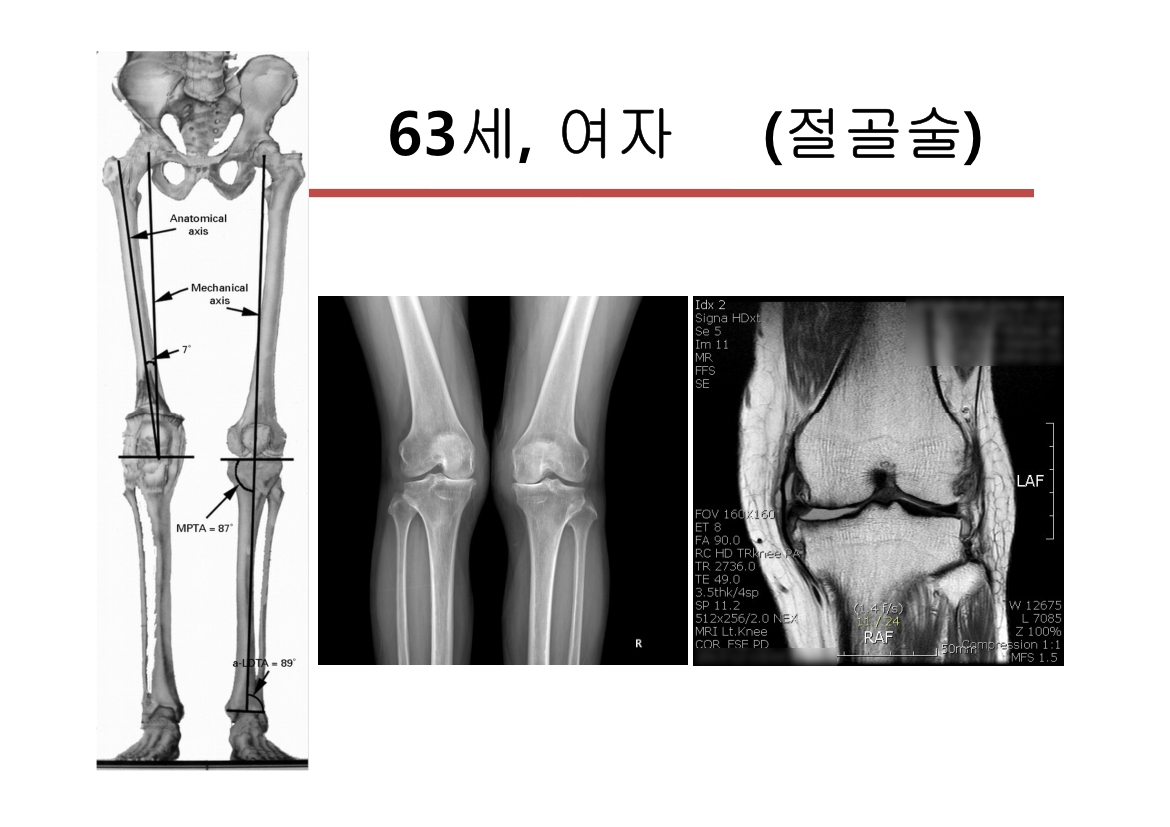

윤정로 병원장님 퇴행성 관절염 치료 자료

윤정로 병원장님의 퇴행성 관절염 치료 관련 자료 입니다.